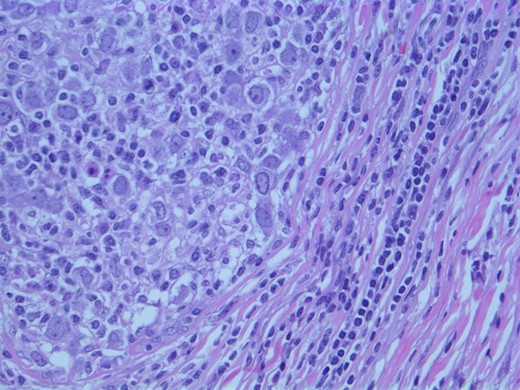

A computed tomographic (CT) scan of her chest with contrast revealed moderate right axillary lymphadenopathy and a lesion in the upper outer quadrant of the right breast measuring 1.3 × 1.2 cm (Fig. 1). A positron emission tomography (PET) scan showed a small intense focus on the right lateral breast consistent with carcinoma, significant right axillary lymphadenopathy and intense fluorodeoxyglucose hypermetabolic activity consistent with metastatic spread. Additionally, enlarged lymph nodes extending along the upper chest wall just inferior to the subclavian vessels and posterior to the pectoralis muscles were seen. A needle biopsy of the mass revealed an extensive involvement of poorly differentiated infiltrating carcinoma (Fig. 2). The tumor showed large nuclei with eosinophilic cytoplasm and prominent nucleoli consistent with apocrine differentiation (Fig. 3). There was a significant inflammatory response to the infiltrating tumor noted. No lymphovascular invasion was identified within the core biopsies. The specimen was estrogen and PR negative as well as HER-2/neu negative.

Photomicrograph: apocrine differentiation and inflammatory response.